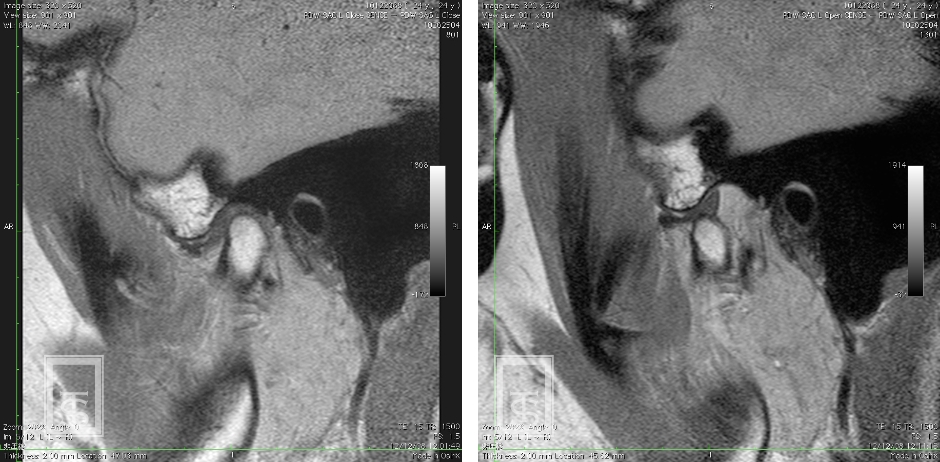

顎関節内障とは?

顎関節内障とは顎関節に器質的変化のある状態(関節円板の転位および下顎頭骨変化)をさします。

一般的に復位性円板転位では、開口時の関節雑音を伴い、非復位性円板転位では、開口障害を生じます。

慢性化すると症状は様々です。

- 検査

- 顔貌、口腔内、模型、機能、レントゲンなどの診査を行います。

必要に応じてCT、MRIの撮影も行います。